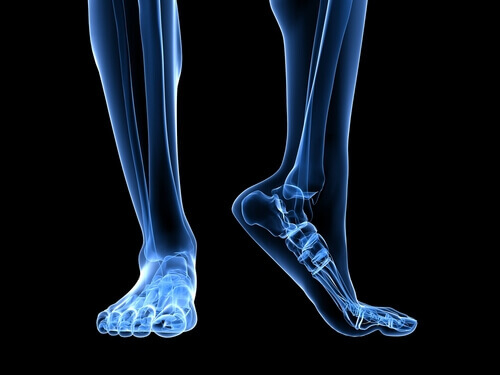

Jalan anatomiaa

On monia sellaisia anatomisia rakenteita, joilla on rooli alueen liiallisessa rasittamisessa.

Akillesjänne on nivelside, joka yhdistää gastrocnemius -lihakset (jotka tunnetaan arkikielessä pohkeina) ja soleusm -lihakset kantapääluuhun. Kutistuminen akillesjänteessä saa aikaan lisääntymisen kantapääluun kokemassa paineessa, ja samoin ilmenee lisääntymistä siinä paineessa, joka kohdistuu jalkapohjan jännekalvoon.

Toinen tekijä, joka kannattaa ottaa huomioon jalan rakennetta koskien, on se, millä tavalla jalka koskettaa maata. Tasaisella maalla jalkapohjalla on taipumus ylipronaatioon, ja jalkapohjan jännekalvo tulee tällöin venytetyksi enemmän, mikä lisää riskiä repeytymiselle, sillä kudokseen kohdistuu enemmän painetta.